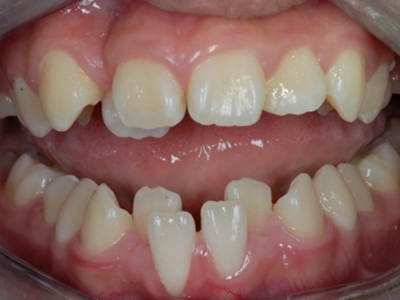

阻生牙是指由于邻牙、骨或软组织的阻碍而只能部分萌出或完全不能萌出,且以后也不能萌出的牙。引起牙阻生的成因,主要是由于颌骨缺乏足够的空间容纳全部恒牙。常见的阻生牙为下颌第三磨牙、上颌第三磨牙及上颌尖牙。

阻生牙可反复引起冠周炎,或引起邻牙牙根吸收和破坏,位置不正,不能完全萌出,好发部位是上、下颌第三磨牙。